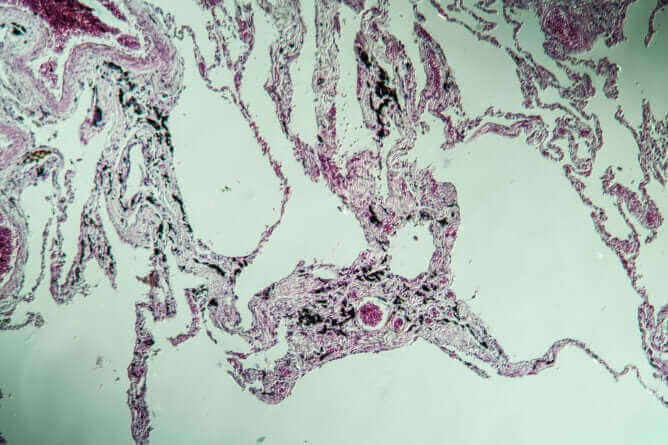

Hinter der Asbestose verbirgt sich eine Fibrosierung des Lungengewebes. Normalerweise ist der Mensch dazu in der Lage, Partikel, die in die Lunge eindringen, durch das Aushusten wieder abzusondern und somit die Lunge zu reinigen. Dies geschieht, indem die Partikel durch die sogenannten Flimmerhärchen abgefangen werden, bevor sie tiefer in die Lunge eindringen und zurück in die Atemwege geführt werden, wo sie ausgehustet werden.

Asbestfasern sind jedoch so fein, dass diese den natürlichen Abwehrmechanismus des Körpers umgehen können und tiefer in die Lunge vordringen, wo sie sich über Jahrzehnte hinweg ablagern und Schäden verursachen können. Hierbei bildet sich krankhaftes Bindegewebe, so dass das Gewebe der Lunge eine Vernarbung und Verhärtung unterläuft. Dadurch wird die Funktion der Lunge permanent eingeschränkt, ebenso steigt das Krebsrisiko erheblich.